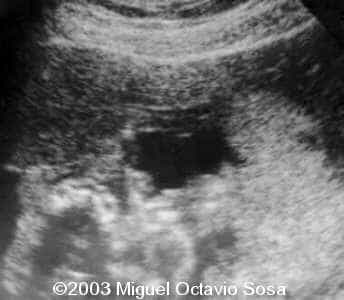

19-year-old primigravida. During third week of pregnancy, she is vaccinated with anti-measles vaccine, without knowing about the pregnancy. There are no important details before the pregnancy. These are images of the face of the fetus. Pay specific attention to the midface.

19-year-old primigravida. During third week of pregnancy, she is vaccinated with anti-measles vaccine, without knowing about the pregnancy. There are no important details before the pregnancy. At 22nd week, an ultrasound is performed demonstrating a single nasal channel on the left side and absence of right nostril.